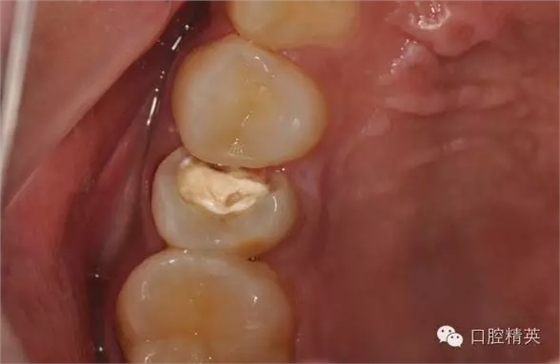

檢查:25近中鄰頜面暫封物,叩痛(-),無(wú)松動(dòng),牙髓活力喪失,牙齦顏色正常

診 斷:25牙體缺損

圖1修復(fù)前頜面觀